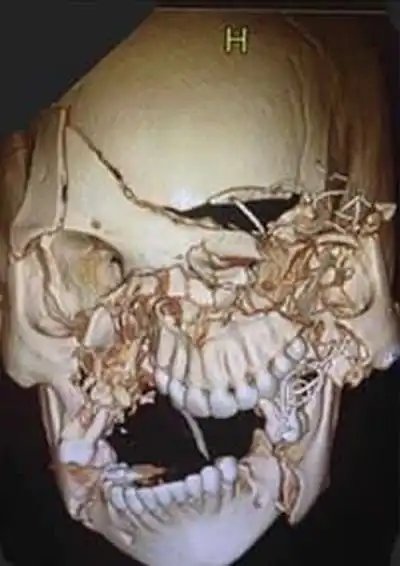

Американский хирург-офтальмолог показал снимки черепа 24-летней девушки, попавшей в серьезную аварию. Из-за того что девушка не была пристегнута ремнем безопасности, она получила множественные переломы черепа и внутричерепное кровоизлияние. Более 8 часов врачи заново собирали череп девушки, скручивая между собой отдельные фрагменты. По словам врача, сейчас девушка уже идет на поправку и чувствует себя хорошо, но чтобы с вами никогда не было ничего подобного, всегда пользуйтесь ремнями безопасности.

До операции